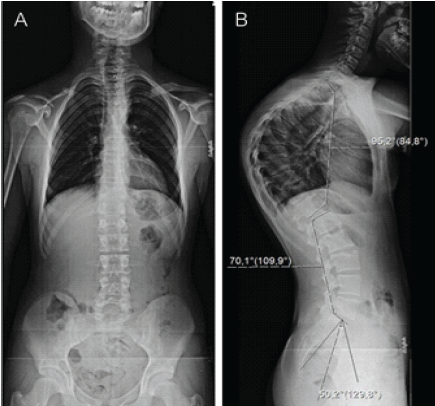

Physical examination revealed a marked and fixed thoracic kyphosis that did not correct with active extension or positional changes. No clinical evidence of scoliosis or neurological deficit was identified. At the time of presentation, the patient’s skeletal maturity corresponded to Risser stage 4. Standing lateral full-length spine radiographs demonstrated thoracic hyperkyphosis with a Cobb angle of 95° (Fig. 1). Magnetic resonance imaging findings were within normal limits.

Figure 1: Full-length spine radiographs (a) – anteroposterior view and (b) – lateral view of thoracic hyperkyphosis with a 95° Cobb angle.